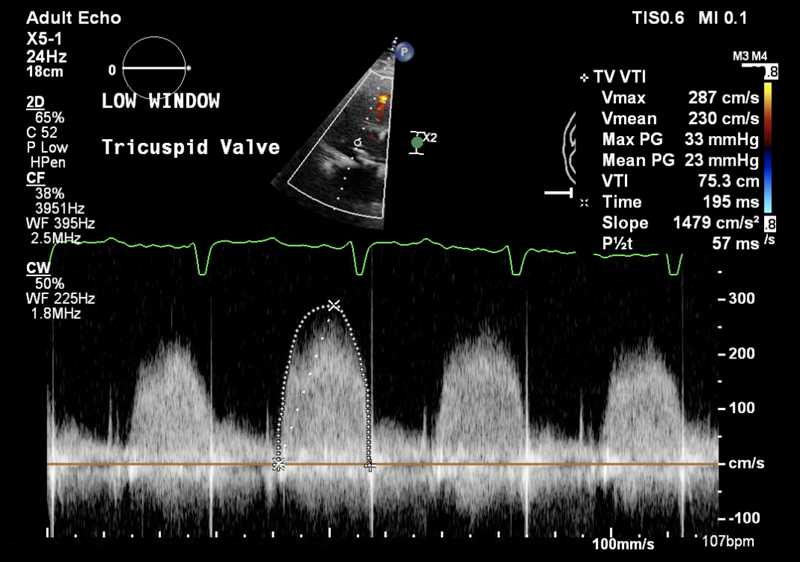

A 32-year-old man presented with worsening symptoms of right heart failure, including fatigue, dyspnea, abdominal swelling, and lower extremity edema. He has a history of tricuspid valve replacement in 2016. He underwent two other sternotomies due to bioprosthetic tricuspid valve failures in 2017 and 2020. Transesophageal echocardiography (TEE) revealed severe stenosis of the bioprosthetic tricuspid valve with a mean gradient of 23 mmHg and mild regurgitation (Figure 1). His left ventricular size, systolic function, and wall motion were preserved. Given his complex surgical history of three sternotomies and decompensated right heart failure, a transcatheter approach was chosen by the heart team. The patient underwent a successful transcatheter TViV procedure using a 29 mm Edwards Sapien S3 valve. This resulted in significant hemodynamic improvement, with the mean gradient across the tricuspid valve decreasing from 23 mmHg to 8 mmHg without paravalvular leak.

Figure 1

Figure 1. Transesophageal echocardiography (TEE) with continuous wave Doppler demonstrating a mean gradient of 23 mmHg of the tricuspid valve.